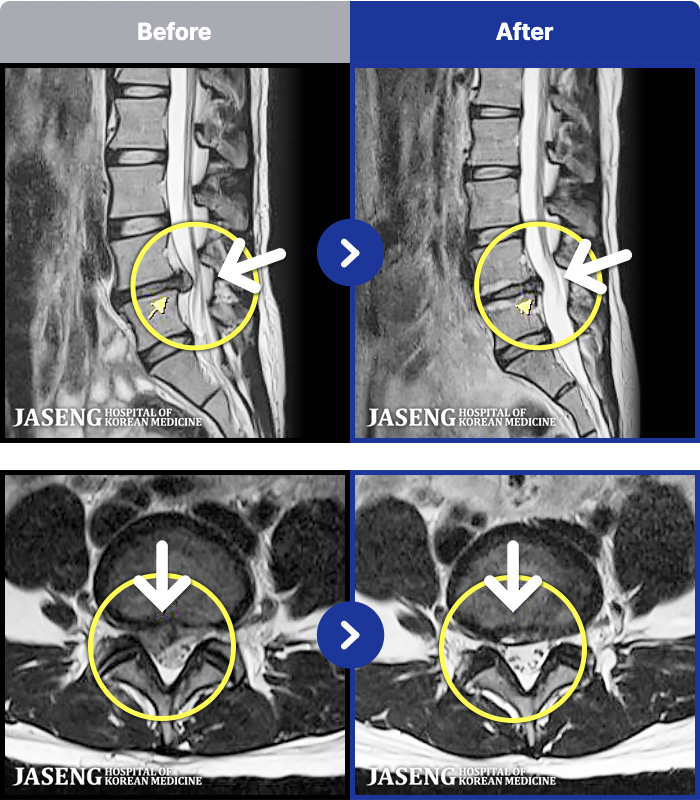

95 MRI ũ ʸ Ȯϼ.

ȯںп Ǹ ǿ ԿǾ, ο ġ ۿ Ƿ ġḦ Ͻñ ٶϴ.